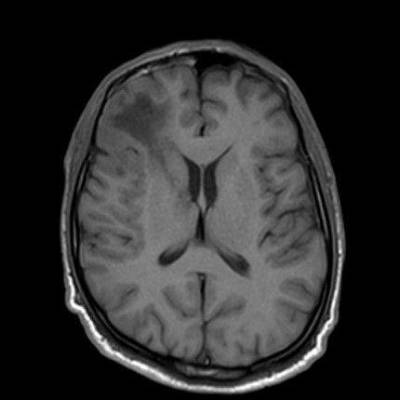

1. A) Aksiyel T2A görüntülerde bilateral sağda belirgin frontoparietal subkortikal ve derin periventriküler beyaz cevherde subkortikal U fiberleri boyunca yerleşimli sinyal artımları (oklar) izlendi.  Tarifli alanlar aksiyel T1A serilerde hipointens görünümde (oklar) izlendi.

1. PML’de MRG bulguları genellikle multifokal, asimetrik periventriküler ve subkortikal beyaz cevher tutulumu şeklindedir. Subkortikal U-fiberleri sıklıkla tutulur, özellikle parietooksipital bölgelerde belirgin lezyon eğilimi vardır.

2. T1 ağırlıklı görüntülerde tutulan bölgeler hipointens, T2A’da ise hiperintens izlenir. Ana lezyon çevresinde çok sayıda noktasal (milkyway) sinyal artımları görülebilir. Ayrıca spleniumu çaprazlayan parietooksipital sinyal değişiklikleri (barbell bulgusu) ve dentat nukleusu koruyarak serebellar beyaz cevher tutulumu (shrimp bulgusu) da tanımlanmıştır.

4. Bizim hastamızda bilinen HIV enfeksiyonu mevcuttu ve yapılan kraniyal MR görüntülemede multifokal, asimetrik, periventriküler ve subkortikal beyaz cevherde yerleşimli, kitle etkisi göstermeyen ve kontrastlanmayan lezyonlar izlendi. Lezyonların subkortikal U-fiberleri tutması ve özellikle parieto-oksipital bölgelerde belirgin olması nedeniyle ön planda PML düşünüldü. Histopatolojik tetkik ile PML tanısı doğrulandı.